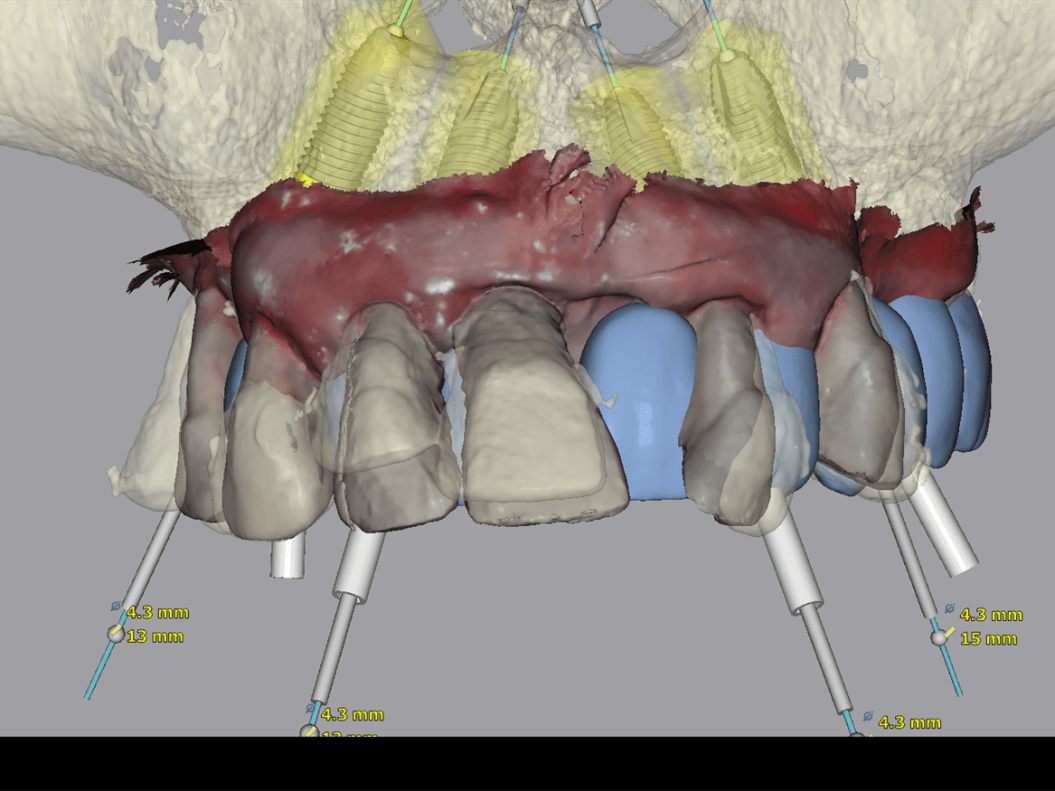

- Tecnologia digitale e intelligenza artificiale – oggi inseriamo gli impianti con sistemi computer-guidati, tramite navigazione dinamica. Questo aumenta la precisione, la sicurezza e il risultato estetico. Non sono necessarie dime chirurgiche né ausili aggiuntivi. Grazie a questa tecnologia, gli impianti vengono posizionati nella sede ottimale per ogni paziente.

- Pianificazione digitale del nuovo sorriso